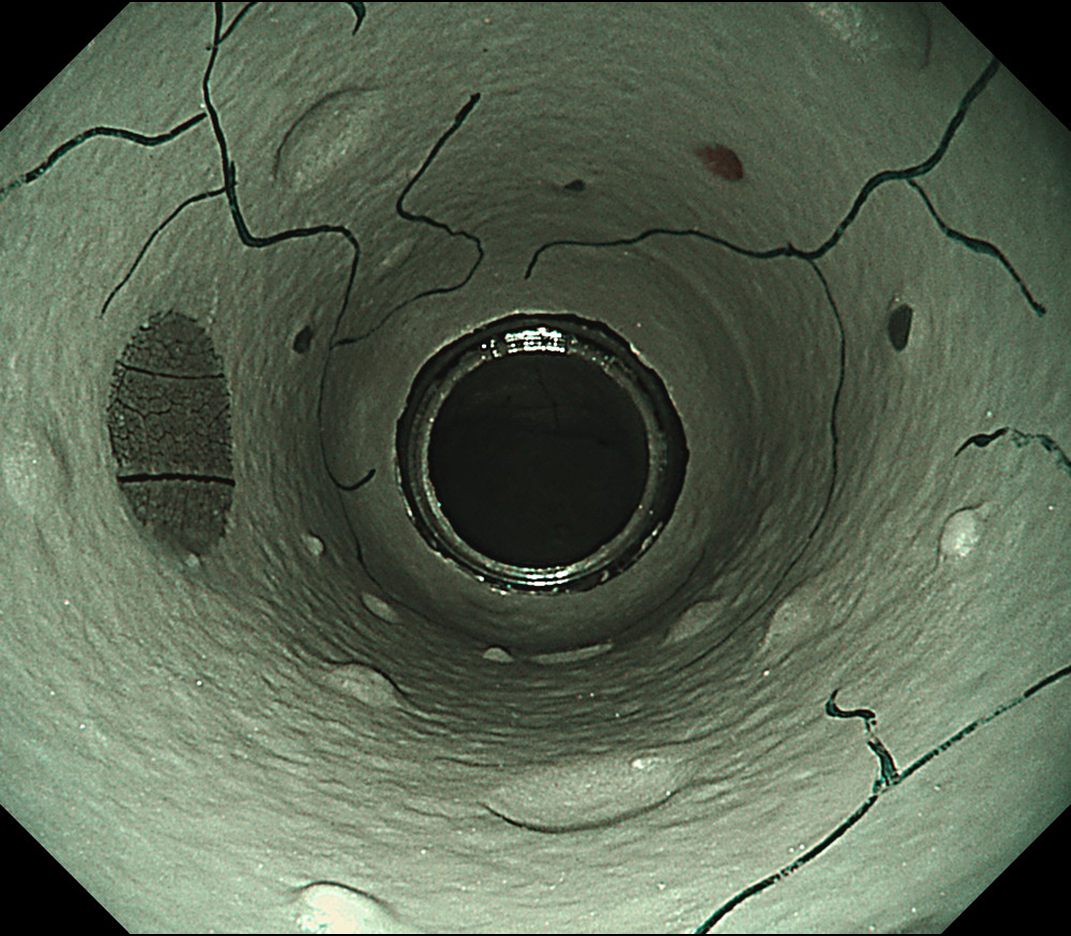

EVIS LUCERA ELITE × GIF1200N 症例画像

遠景部分において明るい視野が確保できる(病変の例)

EVIS LUCERA ELITE×GIF-1200N